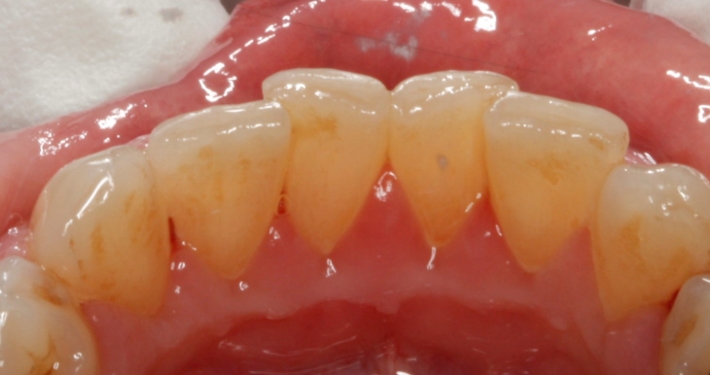

Mehr zu symptomen diagnose behandlung komplikationen ursachen und prognose lesen. Das risiko einer hiv übertragung ist erhöht wenn sich besonders viele viren im blut und den körperflüssigkeiten befinden. 50 prozent der hiv positiven und bis zu 80 pro zent der aids patienten weisen hiv bedingte veränderungen im mund rachenraum auf. Es gibt jedoch situationen wie hiv über den mund zu einer hiv infektion führen kann.

Bei der hiv infektion sind viele systeme und organe betroffen die wachsende hemmung der zellulären immunität die die lebendige identität ihrer evolution klinische manifestationen und labortests bestimmt.

Bei sekundärer immundefizienz beginnt die aktive reproduktion der opportunistischen und pathogenen flora. Broschüre beratung leben mit hiv med info 13 länger leben älter werden mit hiv. Weiterhin können sie ein hinweis darauf sein dass sich die hiv infektion verschlechtert und ins stadium aids übergeht. Die se reichen vom häufig vorkommenden pilzbefall.